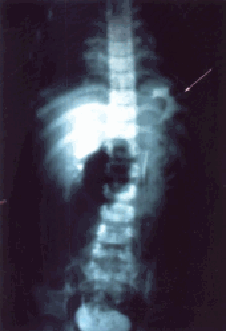

2) de 1 fue pH:7,35; PCO2: 27 mmHg; PO2: 200 mmHg; exceso de base: -8,6; HCO3: 15 mEq/L; saturación: 99,3. El cultivo de sangre demostró Klebsiella sp.A los 4 días de edad, fue sometido a laparotomía. En el acto operatorio se observó un defecto diafragmático posterolateral izquierdo de 5 cm de diámetro. El estómago, bazo, intestino delgado e intestino grueso estaban dentro del hemitórax izquierdo. El intestino estaba malrotado. El pulmón era hipoplásico (aproximadamente 1/3 del tamaño normal). El riñón izquierdo estaba dentro del tórax pero por fuera de la pleura parietal (Figura 2 y 3). El defecto diafragmático fue reparado después de reducir el contenido herniario del hemitórax izquierdo, y el riñón fue dejado dentro del hemitórax porque estaba localizado por fuera de la pleura parietal. Se practicó apendicectomía profiláctica.

Figura 2. Representa una sección sagital izquierda del tronco donde se observa un defecto diafragmático posterolateral y el riñón izquierdo dentro de la cavidad torácica pero por fuera de la pleura parietal.

(5), Ho y col. (7), Hallisey y Caride (35) pertenecen a esta variedad.b. En la segunda, el riñón está dentro de la cavidad torácica pero por fuera de la cavidad pleural (Figura 2), y no forma parte del contenido herniario. Cuando el contenido herniario es reducido, el riñón torácico se muestra a través de la pleura parietal posterior como masa sólida intratorácica de forma arriñonada. El caso reportado aquí por nosotros pertenece a esta variedad.